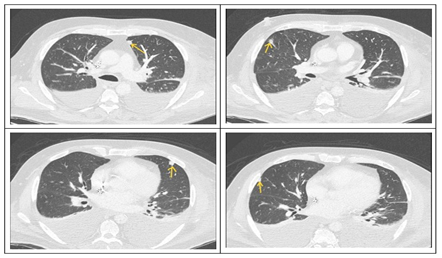

Given the presence of an intracardiac device and persistent MRSA bacteremia, both transthoracic and transesophageal echocardiography (TTE and TEE) were promptly performed. These showed no evidence of valvular vegetations or leadassociated infection. Nevertheless, the ongoing positivity of blood cultures raised concern for disseminated opportunistic infections. A contrast-enhanced full-body CT scan revealed multiple bilateral pulmonary nodules consistent with septic emboli (Figure 1), as well as a chronic right subdural hematoma and a hyperdense focus in the right frontal region. Whole-body 18F-FDG PET/CT (Figures 2,3) demonstrated no abnormal uptake at the pacemaker pocket or along the leads, but revealed increased metabolic activity in the D11 vertebral body (SUV max 12.9), and in the right talus, tarsal bones, and surrounding soft tissues of the lateral malleolus (SUV 7.8) findings suggestive of vertebral osteomyelitis (spondylodiscitis) and chronic osteomyelitis, respectively. Additionally, a reversed liver-to-spleen metabolic gradient (spleen SUV 5.4) was observed, likely reflecting reactive inflammatory changes.

Figure 1: CT scan revealed multiple subcentimeter-sized pseudonodular formations in the expanded lung parenchyma, some of which are triangular, suspicious for septic emboli.